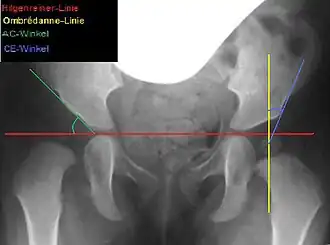

Bemessen wird die laterale Überdachung am sogenannten Acetabulumwinkel (AC-Winkel) im Beckenübersichtsröntgenbild: Ein Winkel zwischen einer Horizontalen durch die Y-Fugen und einer Linie entlang des Pfannenerkers. Beim gesunden Neugeborenen beträgt der AC-Winkel etwa 25°, mit 6 Jahren etwa 15° und ab dem 12. Lebensjahr 11–12°.[3] Entsprechend dieser physiologischen Werte sollte der AC-Winkel auch bei der Acetabuloplastik korrigiert werden. Man spricht von anatomischer Rekonstruktion.[3]